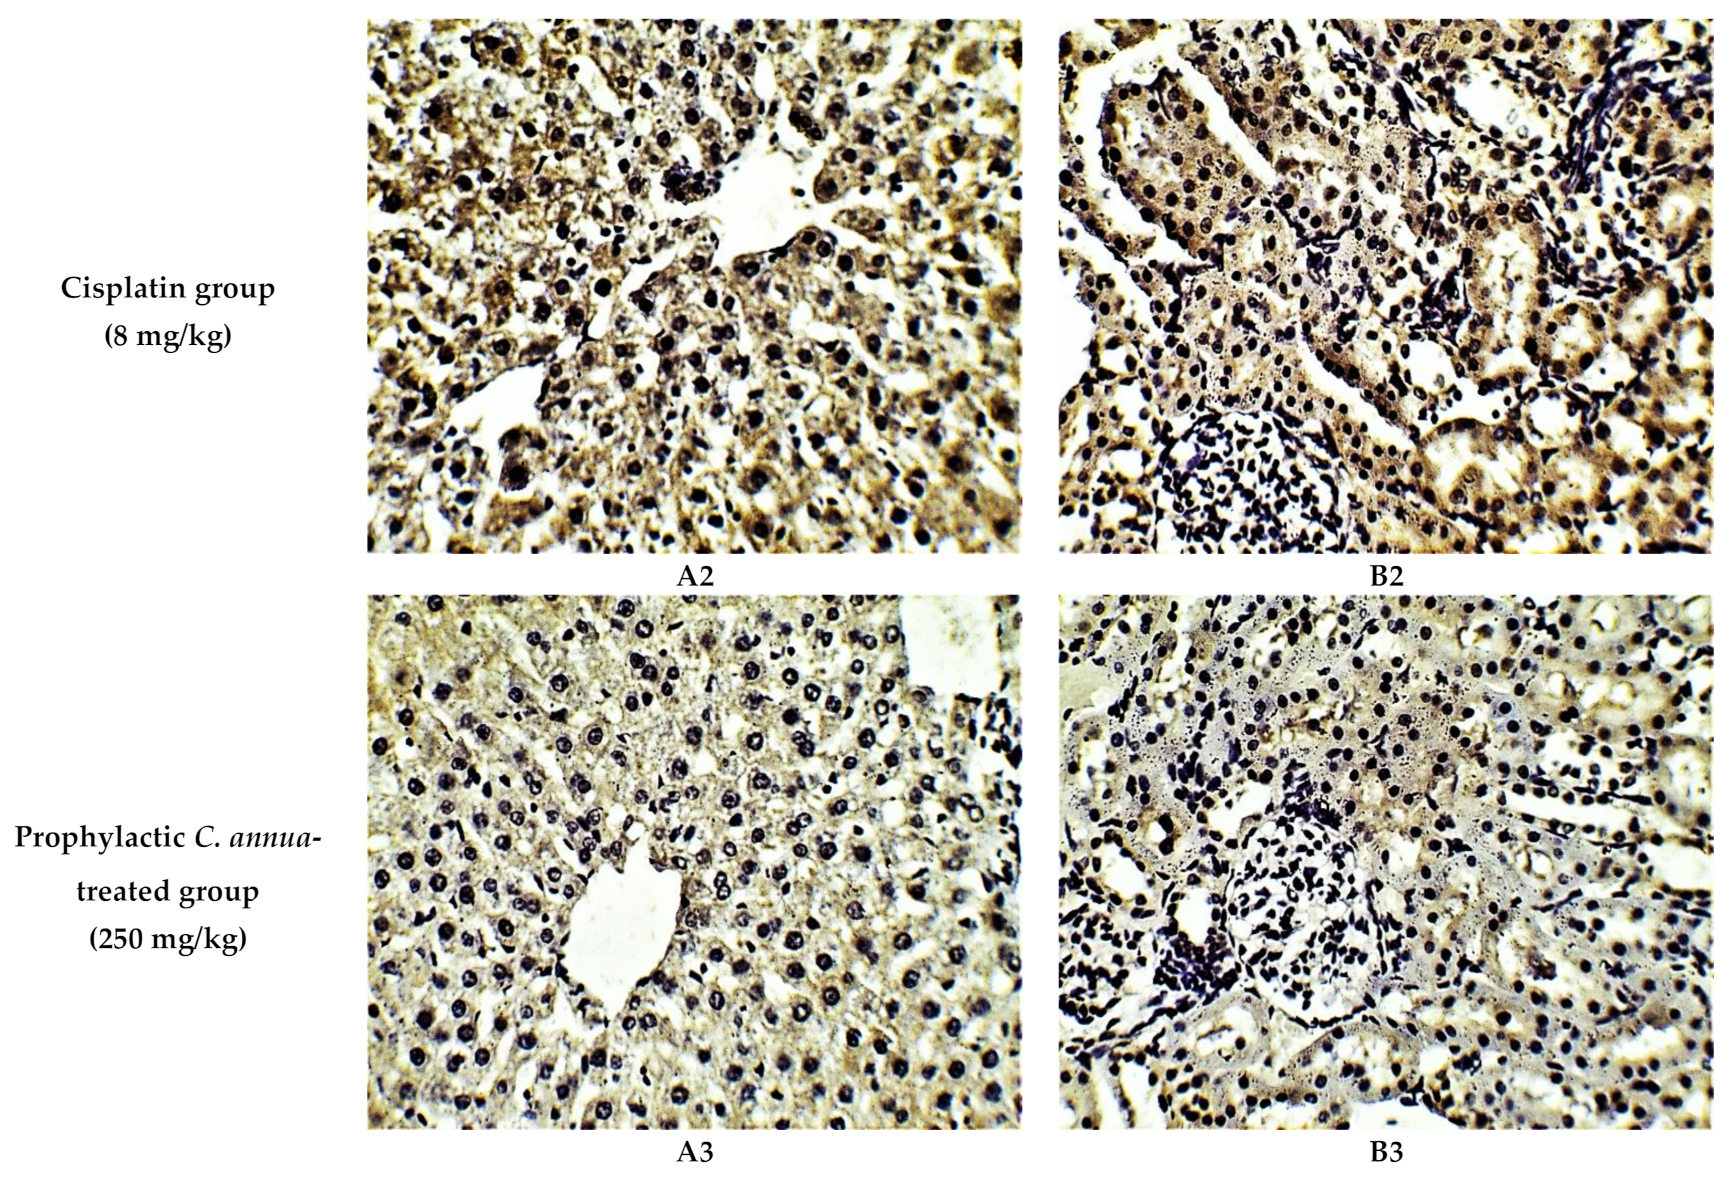

The protective effect of C. annua extract against cisplatin sparked inflammation and apoptosis in renal and hepatic tissues was further confirmed by immunohistochemistry (IHC) where the expression of both IL-1β (an inflammation marker) and caspase-3 (an apoptosis marker) were investigated. Cisplatin group exhibited pronounced expression of IL-1β and caspase-3 in both renal and hepatic tissues of cisplatin treated group compared to the normal control group. Pretreatment with C. annua extract before cisplatin injection has noticeably reduced IL-1β and caspase-3 expression in both kidney and liver tissues in comparison with the cisplatin group (Figure 3, Figure 4, Figure 5).

Figure 3.

Representative photomicrographs (×400) of immuno-histochemical staining of IL-1β in liver (A) and kidney (B) tissues of the experimental groups. (A1) liver tissues of normal control group, (A2) liver tissues of cisplatin group, (A3) liver tissues of Prophylactic C. annua- treated group, (B1) kidney tissues of normal control group, (B2) kidney tissues of cisplatin group, (B3) kidney tissues of Prophylactic C. annua- treated group.

(A) Level of IL-1β expression in liver and kidney tissues of the experimental groups. Positive proportions of IL-1β expression were increased significantly in liver and kidney of cisplatin treated rats compared to the normal control and C. annua pretreated group. (B) Level of caspase-3 expression in liver and kidney tissues of the experimental groups. Positive proportions of caspase-3 expression were elevated remarkably in liver and kidney of cisplatin treated rats compared to the normal control and C. annua pretreated group. Data are represented as mean ± SE and analyzed using ANOVA followed by Bonferroni’s post-hoc test at p value < 0.05, n = 15 for each group. a indicates the presence of significant difference from normal control group, b indicates the presence of significant difference from cisplatin group.